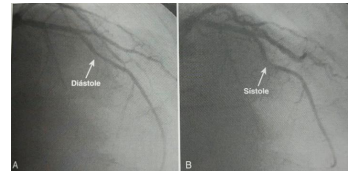

Uma mulher de 45 anos, previamente hígida, apresenta dor anginosa típica, sendo submetida a cineangiocoronariografia, que produz a seguinte imagem:

Fonte: Braunwald – Tratado de Doenças Cardiovasculares – 9ª edição

Dentre as opções abaixo, a que apresenta, respectivamente, a melhor opção terapêutica e a artéria acometida no caso apresentado é: